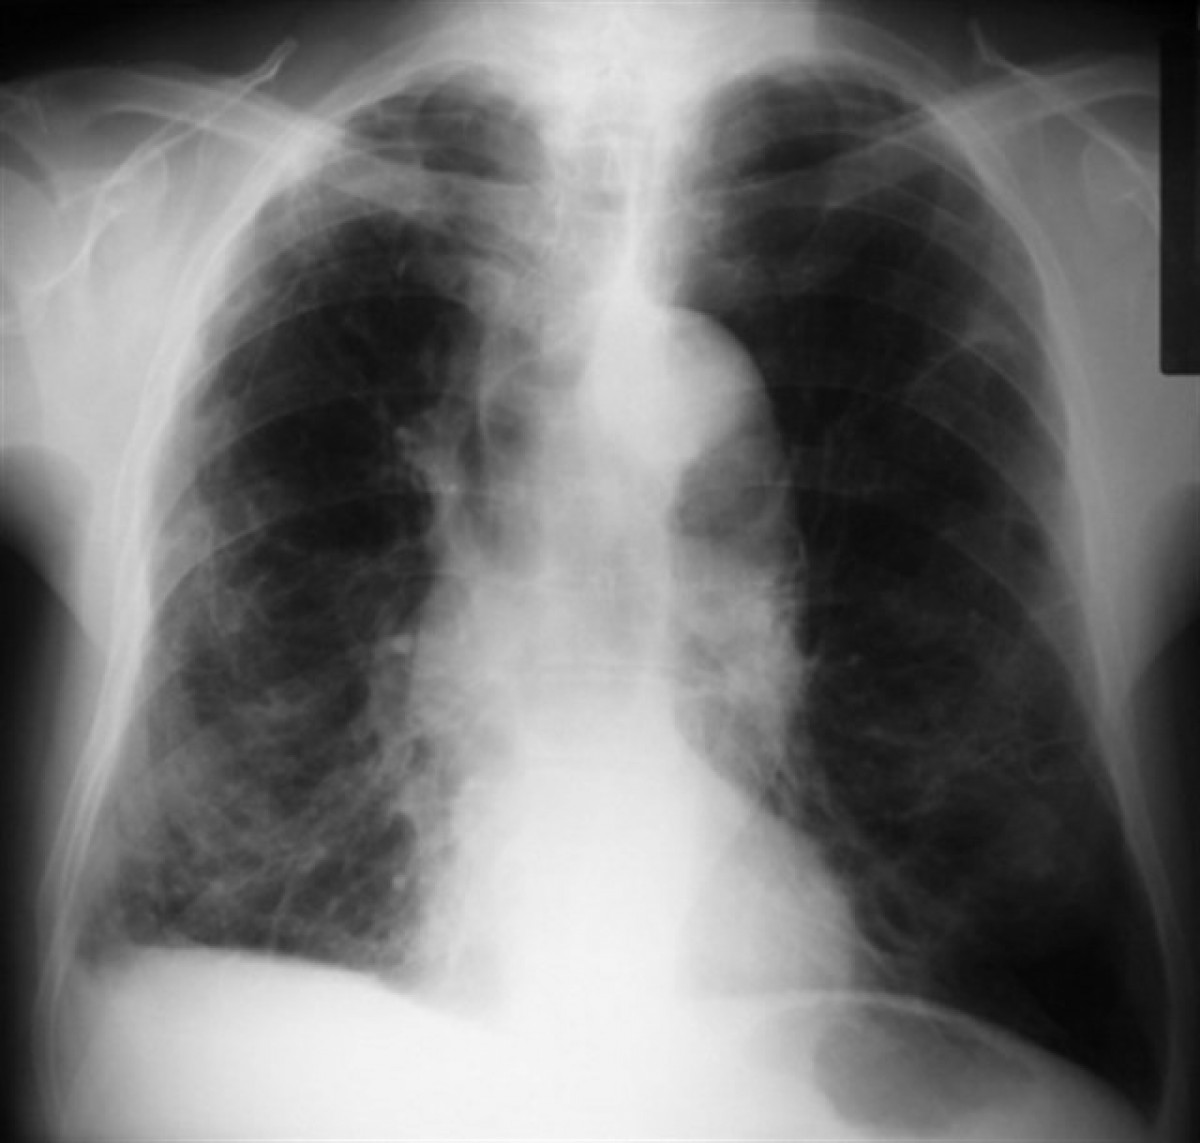

Es tracta d'una patologia respiratòria que es caracteritza per una limitació crònica del flux aeri produïda pel fum del tabac, que presenta una sèrie de canvis patològics en el pulmó i que s'associa amb l'aparició d'altres malalties com, per exemple, les patologies cardiovasculars, càncer de pulmó o osteoporosi.

Els principals símptomes de la EPOC són la tos, que pot ser variable i intermitent; expectoració, sol ser mucoide; i dispnea, complicació que més condiciona la qualitat de vida dels pacients.